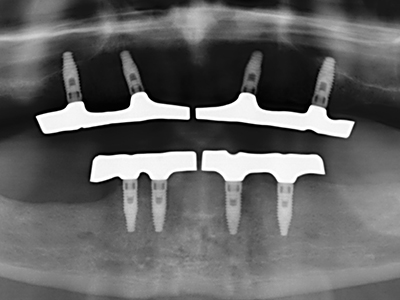

Bone tissue is not simply a mineral structure but also contains a substantial proportion of collagen fibres. This means it not only has good compressive strength but also a degree of flexibility, which can be taken advantage of when performing bone augmentations. In the classical expansion procedure using bone splitting, the atrophied alveolar ridge is split longitudinally and carefully expanded after reaching an adequate osteotomy depth (Fig. 13-16), ideally without substantial removal of the periosteum (Brugnami, Caiazzo et al. 2014, Stricker, Fleiner et al. 2014). Screw and plate systems with increasing expansion distance have proven effective in separating the two bone lamellae while remaining below the fracture threshold. In general, residual bone widths of at least 3–4 mm are required (Chiapasco, Zaniboni et al. 2006) to guarantee adequate flexibility and sufficient bone coverage of the future implants. If necessary, a vertical relief osteotomy on one or both sides can improve flexibility. A combination with additional augmentation techniques, particularly on the buccal side, has been described as an alternative to the classical technique.